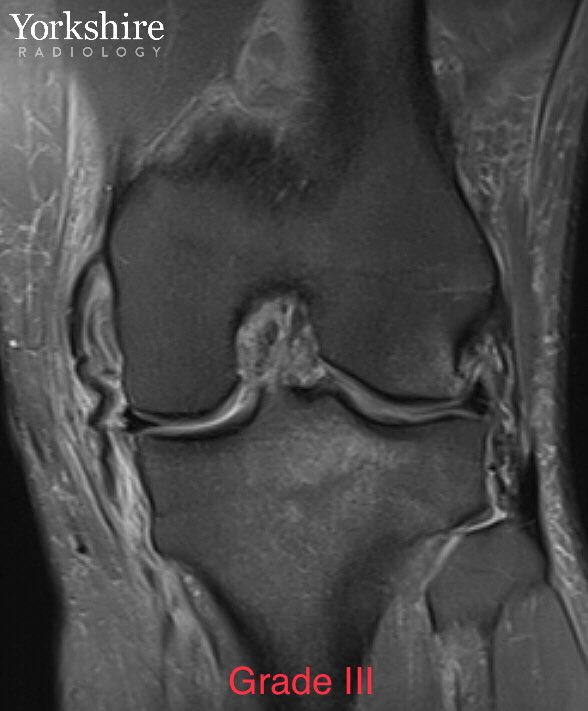

MCL injury gallery. Grade 1, 2 & 3. #orthotwitter